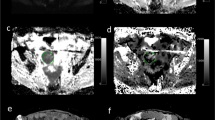

Image analysis

The DKI data were postprocessed by using DWI-Tool software developed by Philips (IDL 6.3, ITT Visual Information Solutions, Boulder, CO. USA)38. Diffusivity and kurtosis maps were calculated with the software by performing a voxel-by-voxel fitting of DKI data on the basis of robust nonlinear least-squares curve fittings based on the Levenberg-Marquardt algorithm using the equation: S = S0·exp(−b·D + b2·D2·K/6), in which S is DWI signal intensity at a particular b value, S0 is the signal intensity when b value is 0 sec/mm2, b represents b-value, diffusivity represents the corrected ADC accounting for non-Gaussian diffusion behavior and kurtosis represents excess kurtosis16. Kurtosis is a unitless parameter with 0 representing perfectly Gaussian diffusion and larger kurtosis representing greater deviation from a Gaussian fitting. The ADC map was calculated using the standard monoexponential fitting with the equation S = S0·exp (−b·ADC) (Fig. 5).

Representative MR images of CRC xenograft tumors in CRC/Control and CRC/ EMT groups. The upper and lower rows were axial T2W, ADC, Diffusivity, and Kurtosis color maps in CRC/Control tumor (arrow) and CRC/ EMT tumor (arrow) in the right hind flank, respectively. The ADC and diffusivity coefficients calculated from lesion ROI of CRC/Control tumor on the corresponding maps were (0.480 ± 0.056) × 10−3 mm2/s and (0.660 ± 0.032) × 10−3 mm2/s, respectively, which were higher than those of (0.383 ± 0.043) × 10−3 mm2/s and (0.447 ± 0.014) × 10−3 mm2/s in the CRC/EMT tumor. Kurtosis coefficient of 1.477 ± 0.061 in the CRC/Control tumor was lower than that of 1.627 ± 0.050 in the CRC/EMT tumor.

Two radiologists (C.Y.Z and J.N.L, with 5 and 3 years of experience in abdominal imaging, respectively), who were blinded to histopathological results, independently measured ADC, diffusivity and kurtosis values on the corresponding maps. Regions of interest (ROIs, range 57–214 pixels) were placed on the center slice of each tumor with a reference to T2W image to avoid the hemorrhagic, cystic, and necrotic areas. Each observer performed two measurements. ICCs computed from observer 1’s or observer 2’s two measurements and ICCs computed from observer 1’s first measurements and observer 2’s first measurements were used to evaluate intra- and inter-observer agreement for ADC, diffusivity, and kurtosis measurements. The mean ADC, diffusivity, and kurtosis values were calculated as an average of four measurements from observer 1 and observer 2.